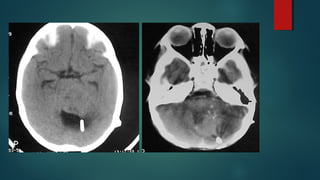

Este documento es el programa para un taller de imágenes del curso de emergencia 2015 impartido por el Dr. Víctor Delgado. El taller se centra en el uso de imágenes médicas para el diagnóstico y tratamiento de pacientes en coma traumático según la base de datos de Marshall. El Dr. Delgado es el único instructor repetido a lo largo del documento.